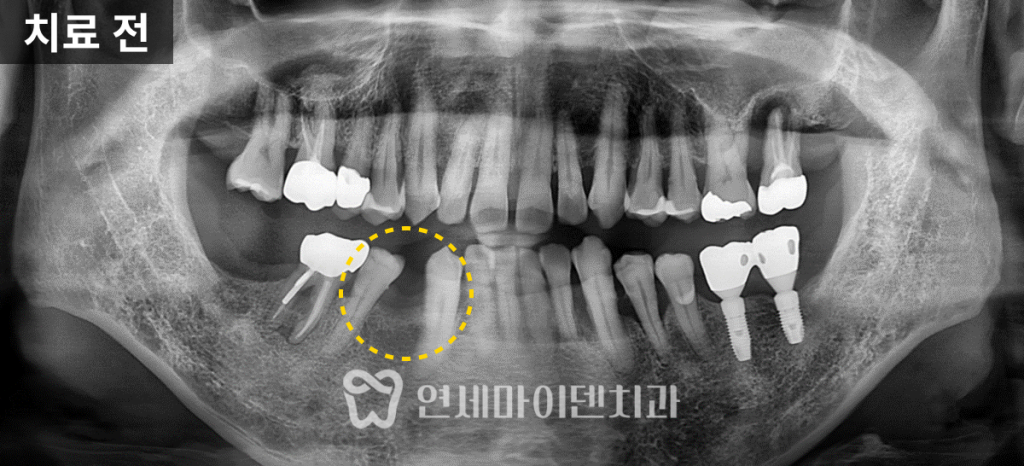

이 환자분은 50대 남성분으로

오른쪽 아래 어금니 2개가 이미 결손된 상태였고,

해당 부위에는 임플란트 식립이 필요했습니다.

하지만 인접한 치아가 옆으로 심하게 쓰러져 있어서,

임플란트를 위한 공간이 전혀 확보되지 않은 상황이었습니다.

방사선 사진에서는 추가적인 골격 문제도 확인됐습니다.

아래턱이 아래로 처지고 턱끝이 덜 발달된

골격성 2급 부정교합이 관찰되었습니다.

치아는 깊게 물리는 과개교합 상태로,

아랫입술이 돌출되어 보였습니다.